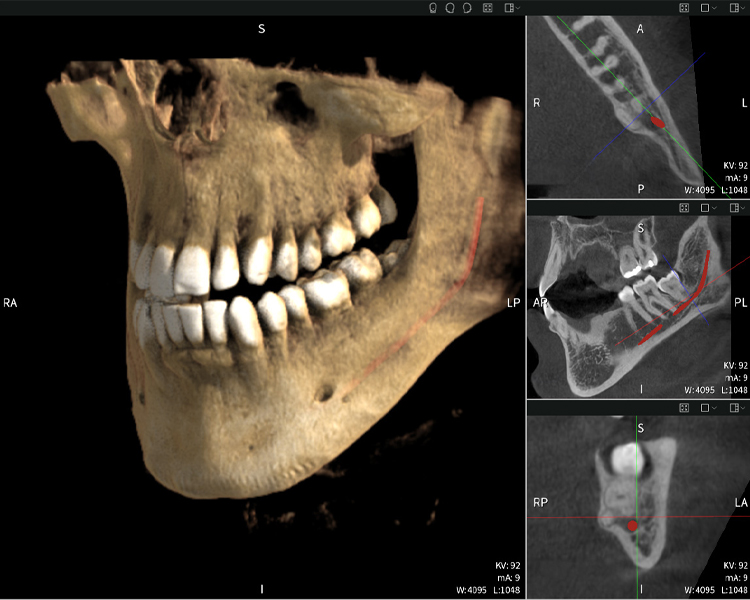

Figure b: Imaging results of Seethrough Max, in front of a black background.

Figure b

Figures b–d show various views of a 3D reconstruction of the mandible, providing a comprehensive overview of the mandibular anatomy, the position of the nerves in relation to the teeth, and allowing assessment of tooth symmetry and alignment.